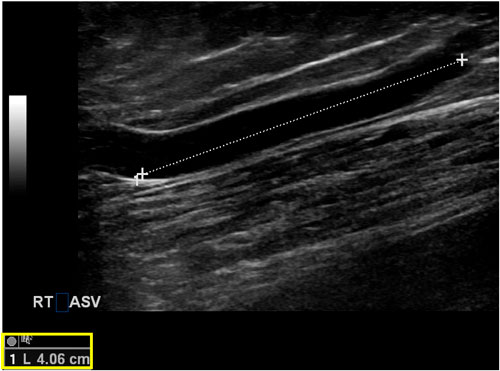

ASV thường ngắn hơn GSV và trong một số trường hợp, nó có thể quá ngắn để đặt cannula phục vụ quá trình can thiệp nội nhiệt. Ở các bệnh nhân béo phì, có thể khá khó khi xác định vị trí, đặt cannula và điều trị ASV vì nó có thể xuyên qua mạc hiển và trở thành một nhánh tĩnh mạch giãn ở ngay phía dưới nếp lằn bẹn, nơi khó có thể xác định dễ dàng bằng siêu âm để đặt kim và guidewire. Tumescent cũng có thể khá khó ở những bệnh nhân này. Khi ASV nằm trong khoang hiển, chiều dài của nó có thể ngắn hơn vùng phát nhiệt của dây đốt. Tùy theo nhà sản xuất, một dây đốt với vùng phát nhiệt rộng 2,5 đến 3 cm thường được sử dụng để đảm bảo rằng loại bỏ toàn bộ chiều dài của ASV mà không để da tiếp xúc với bức xạ sóng cao tần (hình 6). Trong những trường hợp này, các kĩ thuật tiếp cận không sinh nhiệt như keo sinh học (cyanoacrylate), tiêm xơ bằng bọt, hoặc hóa cơ học có thể là những lựa chọn bổ sung tốt. Ngoài ra, phẫu thuật thắt cao (high ligation) hoặc cắt bỏ tĩnh mạch đơn thuần cũng có thể được xem xét.